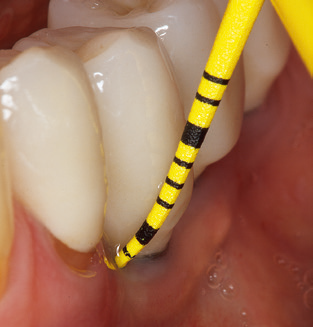

The current working concept for SPT

Fig. 4: Flexible probes with millimetre markings are recommended for the probing of dental implants (e.g. Colorvue Kit PCV11KIT6, Hu­Friedy). – Fig. 5a and b: A straight working tip (1P, W&H Dentalwerk Bürmoos GmbH) is a suitable instrument for use on all natural teeth. – Fig. 6: Curved working tips (3Pr/3Pl, W&H Dentalwerk Bürmoos GmbH) lend themselves to the processing of difficult-to-reach areas of the tooth and root surfaces (e.g. furcations). – Fig. 7: The tapered, hexagonal implant cleaning tip (1I, W&H Dentalwerk Bürmoos GmbH) permits atraumatic and efficient cleaning of the crown and abutment surfaces. – Fig. 8: Titanium and carbon curettes are suitable instruments for the manual cleaning of the implant surfaces.

Of course, working tips for the cleaning of implant surfaces are also indispensable for SPT in patients fitted with implants. The implant cleaning attachment on the system used here is characterised by its tapered, hexagonal design. This design allows light, atraumatic penetration of the peri-implant pocket and displays a good cleaning performance (Fig. 7).